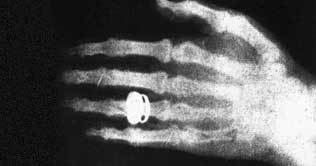

Today is the 115th anniversary of discovery of X-Ray, one of the most important discoveries in the world of science and technology. X-Ray was discovered by Wilhelm Conrad Roentgen, in 1896. One day Wilhelm Conrad Roentgen, while working with a fluorescent light bulb, he evacuated the tube of all air and filled it with gas. He then passed the high electric voltage through it. Suddenly he noticed a fluorescent glow. He covered the tube with a thick sheet of paper but then noticed the light reflect on a screen. He realized the presence of an 'invisible light' which can penetrate through even a screen. His later experiments revealed that this 'invisible light can also penetrate through human body. Thus was the discovery of X-Ray. X-Ray, is an electromagnetic radiation. Wilhelm Conrad Roentgen, explains that X-Ray, is a form of electromagnetic radiation. As the wavelength of the light decreases, it increases in energy. X-Ray lights act more like particles than a wave. The X-Ray machine passes individual X-Ray particles, called photons. These particles pass through the body. A special film is used to record the image. Dense structures like bone and teeth, appear white. Structures containing air like muscle, fat etc appear gray. Roentgen's first experiment was in late 1895. The first film after the discovery of X-Ray was his wife Bertha's hand with a ring on her finger. X-Ray was first utilized clinically in early 1896 in United States. It was called X, as he did not have a name for it. After the discovery of X-Ray, many urged him to name it after his name but he like it to be known as 'X-Ray' and thus it is still named. Today, Google celebrates the 115th anniversary of discovery of X-Ray.